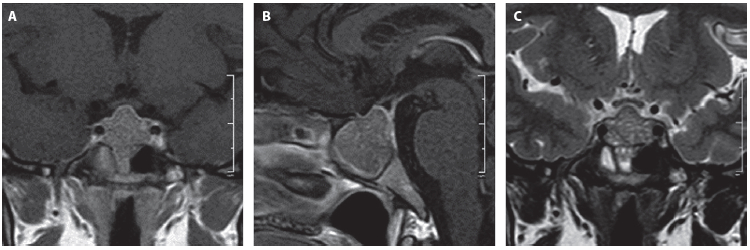

Paciente femenina de 37 años con historia de obesidad grado III, a quien por sintomatología inespecífica de mareos se le realizó una TC cerebral que encontró un hallazgo incidental de masa selar, corroborado por IRM de silla turca con evidencia de una lesión selar compatible con adenoma hipofisario (Figura 1). No tenía evidencia clínica de síntomas por déficit o exceso hormonal, la evaluación neuroftalmológica y los campos visuales fueron normales. El perfil hipofisario mostró como única alteración una leve elevación de la prolactina atribuida al efecto compresivo sobre el tallo hipofisario; se descartó efecto Hook con valores de prolactina diluida (Tabla 1).

Figura 1. Resonancia de hipófisis previa al inicio del tratamiento. A. Secuencia T1 contrastada, corte coronal. B. Secuencia T1 contrastada, corte sagital. C. Secuencia T2, corte coronal. Se identifica una masa cuyo diámetro era de 24 mm anteroposterior x 25 mm longitudinal x 21 mm transverso, con un volumen tumoral de 6,3 mL, en contacto con el quiasma óptico y con extensión al seno esfenoidal.